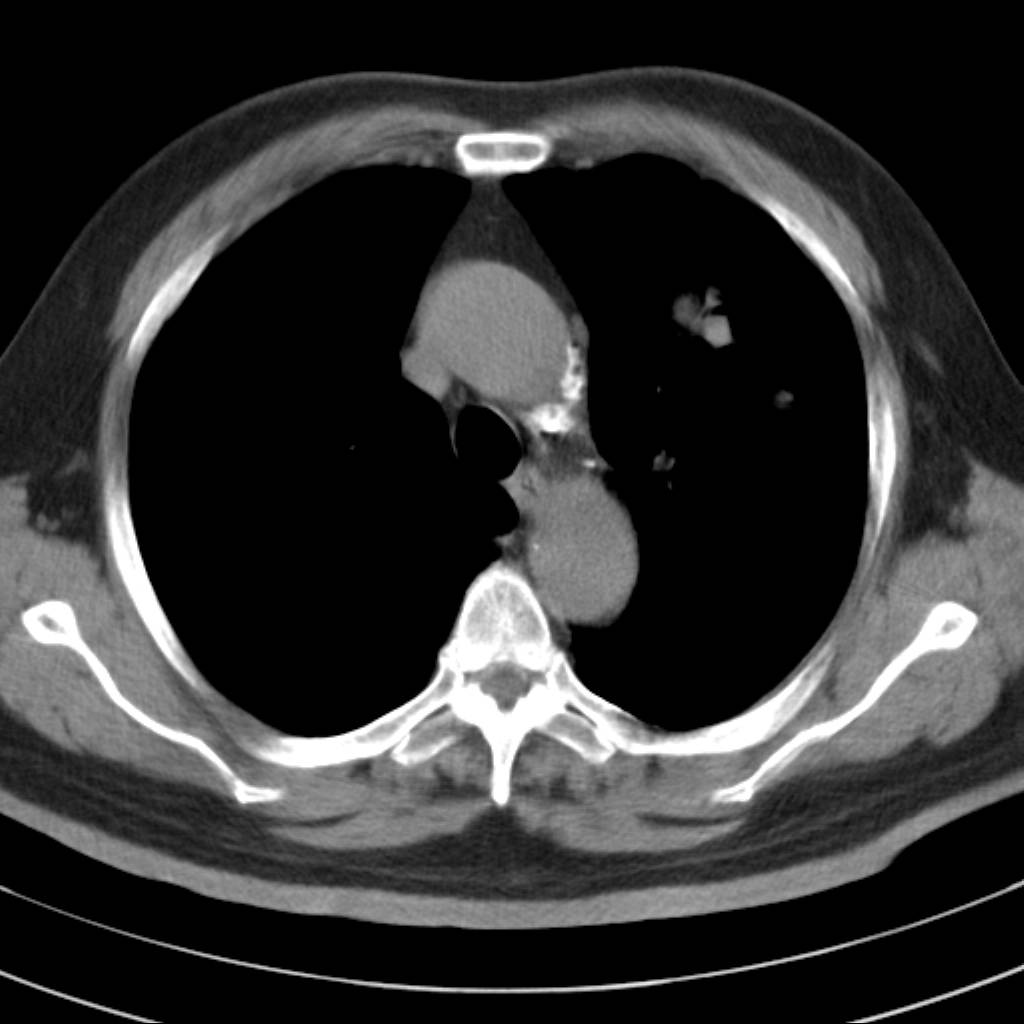

标题: CT18644:男,82岁,体检发现左肺阴影. [打印本页]

标题: CT18644:男,82岁,体检发现左肺阴影.

岁数太大,没有增强。麻烦见过的,给个诊断,顺便再说说病因

左肺动静脉畸形,肺动静脉畸形(pavms)是肺血管发育异常,是肺动脉与肺静脉直接相通形成短路,通常包括一条供血动脉及一条或数条引流静脉,以及他们之间的异常血管团。约70%的患者伴发遗传性出血性毛细血管扩张症。 影像检查的目的在于确定病灶位置、大小、形态、数目。x线可表现为:1.结节型(直径小于3cm)2.团块型(直径大于3cm)3.弥漫型(肺内散在逗点状影),以团块状居多。 ct扫描可见单发或多发肺内结节,有的有蜿蜒迂曲的团块影,边缘光滑、锐利,增强ct扫描可见增粗、扭曲的血管影和/或类圆形的增粗的血管断面,甚至供血动脉及引流静脉。

平扫似avm,建议增强扫描。

肺血管畸形